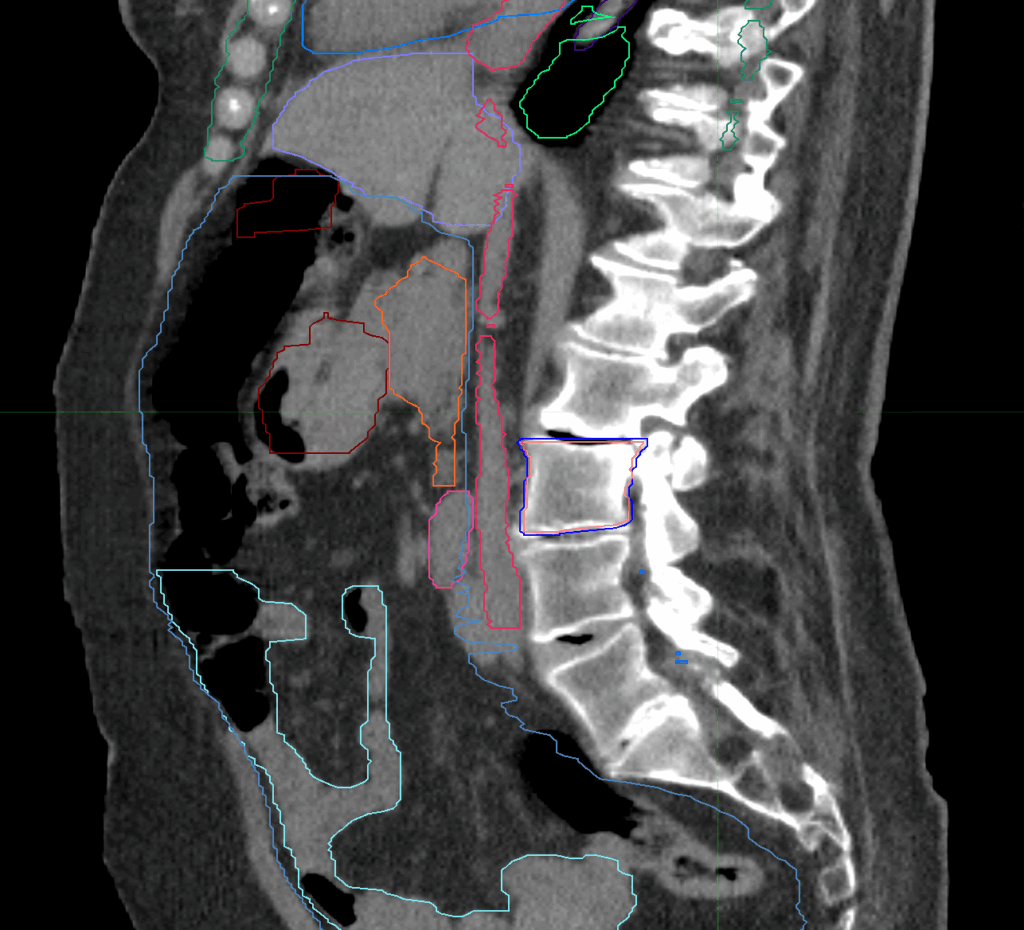

T10-T11 Spine Metastasis

< View All Plan Studies CYBERKNIFE SYSTEM T10-T11 Spine Metastasis Case History AGE: 76-year-oldGENDER: Male Medical History Immidiate tolerance: Grade II dermatitis with eyelid edema, Grade I conjunctivitis resolved with Sterdex Diagnosis: Squamous cell carcinoma of the right lower eyelid Planning CT Images Treatment Plan Images Treatment Planning Highlights Fractionation 27 Gy in 3 fractions […]

L3 Spine Metastasis

< View All Plan Studies CYBERKNIFE SYSTEM L3 Spine Metastasis Case History AGE: 76-year-oldGENDER: Male Medical History Immidiate tolerance: Grade II dermatitis with eyelid edema, Grade I conjunctivitis resolved with Sterdex Diagnosis: Squamous cell carcinoma of the right lower eyelid Planning CT Images Treatment Plan Images Treatment Planning Highlights Fractionation 27 Gy in 3 fractions […]